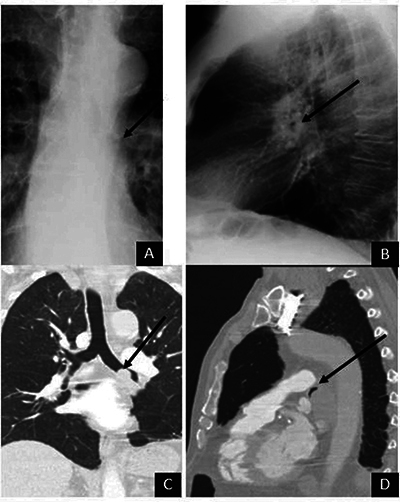

The air crescent (AC) is a common radiological sign. Even if its commonest aetiology remains pulmonary aspergillosis, various other causes have been described. In this study, we report four rare causes of ACs seen on chest radiographs that haven't been described in the literature. Teaching point: The differential diagnosis of an air crescent sign on chest radiographs includes oesophageal bezoar, interstitial lung emphysema, central bronchial stenosis and perforated emphysematous cholecystitis.

空气新月(AC)是一种常见的放射学征象。尽管其最常见的病因仍然是肺曲霉菌病,但也有其他各种病因的描述。在本研究中,我们报告了四种罕见的导致胸片上出现空气新月征的病因,这些病因在文献中还没有出现过。教学要点:胸片上出现气新月征的鉴别诊断包括食道大泡、肺间质气肿、中央支气管狭窄和穿孔性气肿性胆囊炎。